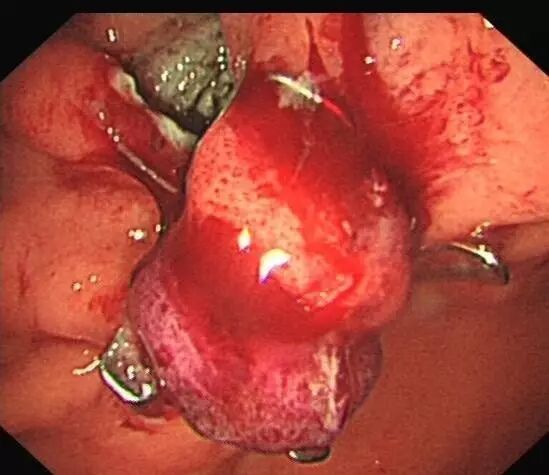

OTSC在消化道出血治疗中的应用

内镜夹怎么不掉CJP每周一帖--OTSC吻合夹系统在经内镜治疗消化道出血、穿孔及瘘中的应用_https://www.jmylbn.com_新闻资讯_第8张